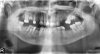

Pacientka27 Опубликовано 22 апреля, 2013 Поделиться Опубликовано 22 апреля, 2013 (изменено) Снимок 1. Изменено 22 апреля, 2013 пользователем Pacientka27 Ссылка на комментарий

Pacientka27 Опубликовано 22 апреля, 2013 Автор Поделиться Опубликовано 22 апреля, 2013 Снимок 2, с предложенной схемой лечения (протезирования). Ссылка на комментарий

Pacientka27 Опубликовано 22 апреля, 2013 Автор Поделиться Опубликовано 22 апреля, 2013 Ответ нужно дать завтра. Смущает удаление семи зубов, пусть и сильно разрушенных. И депульпация верхних 2-х "двоек", с мотивацией, что это "не ценные" зубы, зато будет всё красиво. Ссылка на комментарий

IvanK Опубликовано 22 апреля, 2013 Поделиться Опубликовано 22 апреля, 2013 Ответ нужно дать завтра. Смущает удаление семи зубов, пусть и сильно разрушенных. И депульпация верхних 2-х "двоек", с мотивацией, что это "не ценные" зубы, зато будет всё красиво.все что написано удалять - имеет для этого показания..по двойкам - нужно послушать ортопедов. Ссылка на комментарий

DmitrySH Опубликовано 22 апреля, 2013 Поделиться Опубликовано 22 апреля, 2013 То что удалять - удалять точно. Про двойки не скажу. Ссылка на комментарий